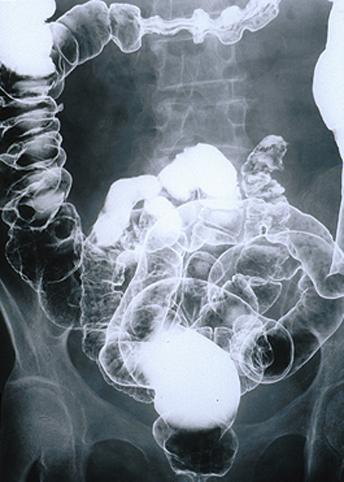

症例提示(所在地,施設名等): 福岡県・ 九州がんセンター

疾患(病理主体)の分類悪性リンパ系腫瘍/MLP型悪性リンパ腫

部位(臓器別)大腸/2区域以上の大腸にまたがるもの

検査方法X-P

病変の最大径(ミリ)10〜14

多発腫瘍(同一臓器)有(同・異時性)